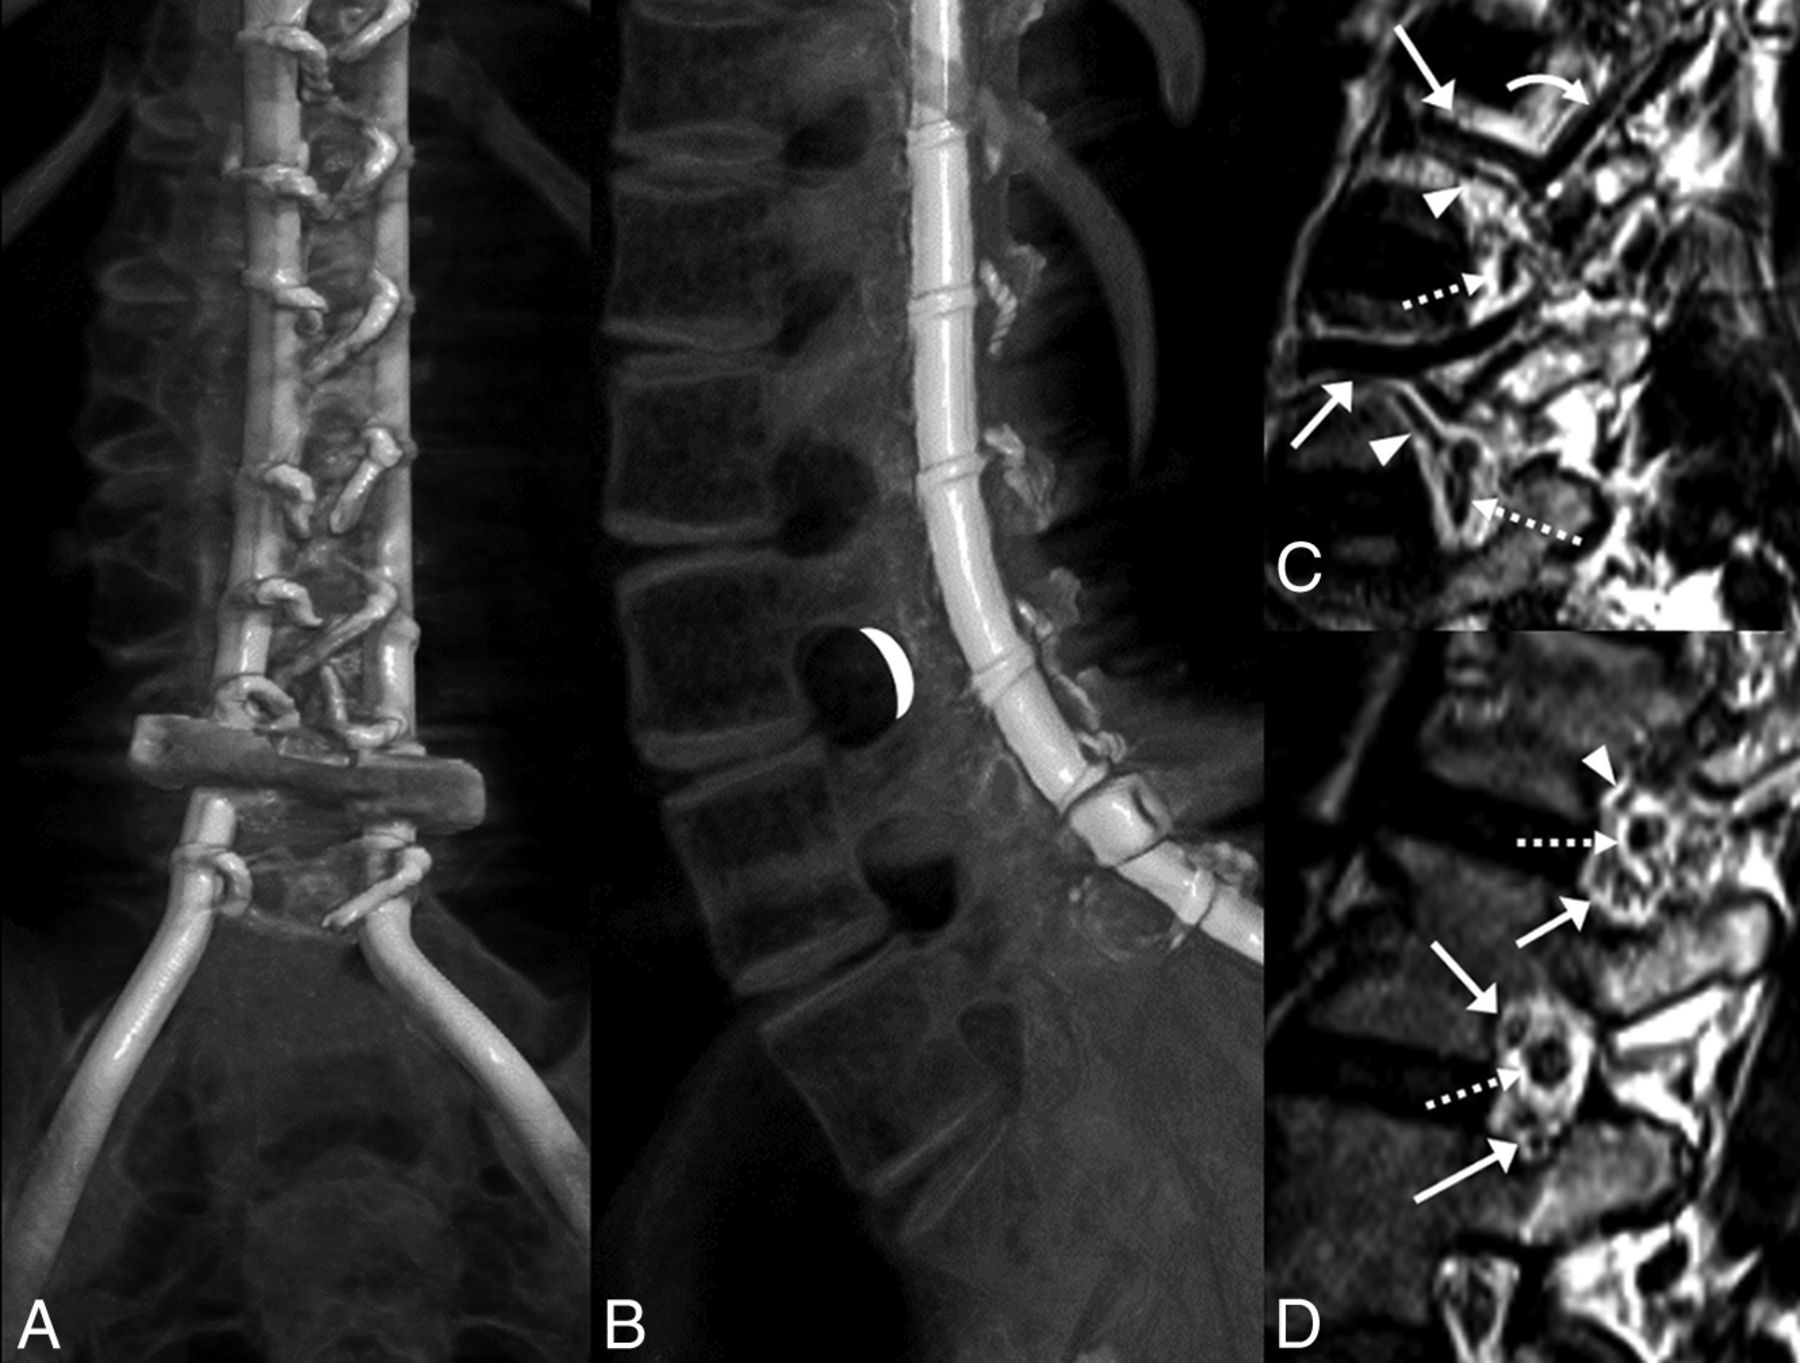

Preprocedural evaluation of lumbar spine radiographs and CT studies revealed extensive spinal fusion hardware and resultant complete osseous interlaminar fusion without any access for classic interlaminar LP (Fig 2). Alternative surgical options discussed with the patients included Ommaya reservoir and lumbar shunt placement (after drilling through the fused laminae). After we discussed the risks and benefits of the different approaches, these 7 patients with SMA decided to proceed with TFLP.

A and B, CT volumetric rendering of a patient with SMA2 demonstrates extensive posterior spinal fusion hardware and complete osseous interlaminar fusion without any access for a classic interlaminar LP. Note the widely patent neural foramina. The white crescent represents the target for TFLP. C and D, Sagittal 3D volumetric T2-weighted images of a healthy person obtained with 3T MR imaging. C, Image obtained slightly lateral to the neural foramen. D, Image obtained at the foramen. Flow voids of the lumbar arteries (arrowheads) and larger caliber lumbar veins (arrows) are seen in the anterior superior aspect of the foramen. A branching ascending lumbar vein is seen coursing toward a higher level neural foramen (curved arrow). More venous structures are seen in the inferior aspect of the foramen (arrows in D). Exiting nerve roots are shown within the center of the foramen (dashed arrows).

When performing TFLP, the proceduralist should be familiar with the anatomic location of the exiting nerve root, the radiculomedullary arteries, and, potentially, the artery of Adamkiewicz. The radiculomedullary branches are in the anterosuperior aspect of the foramen, while the ganglion and exiting nerve root are in the midportion of the foramen (Fig 2). Only smaller branch arteries and veins are found in the posterior aspect of the neural foramen.12 In our method of TFLP, the needle is passed through the posterior portion of the foramen into the spinal canal (Figs 2⇓–4) to minimize the risk of neurovascular injury. Thus, the operator should be proficient with transforaminal procedures as a prerequisite to TFLP.